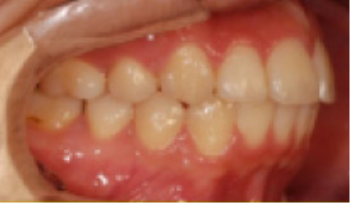

• 하악 전돌(주걱턱) 아래턱이 앞으로 나옴.

Before

After

• 전치부 반대교합 위아래 앞니가 거꾸로 물림.